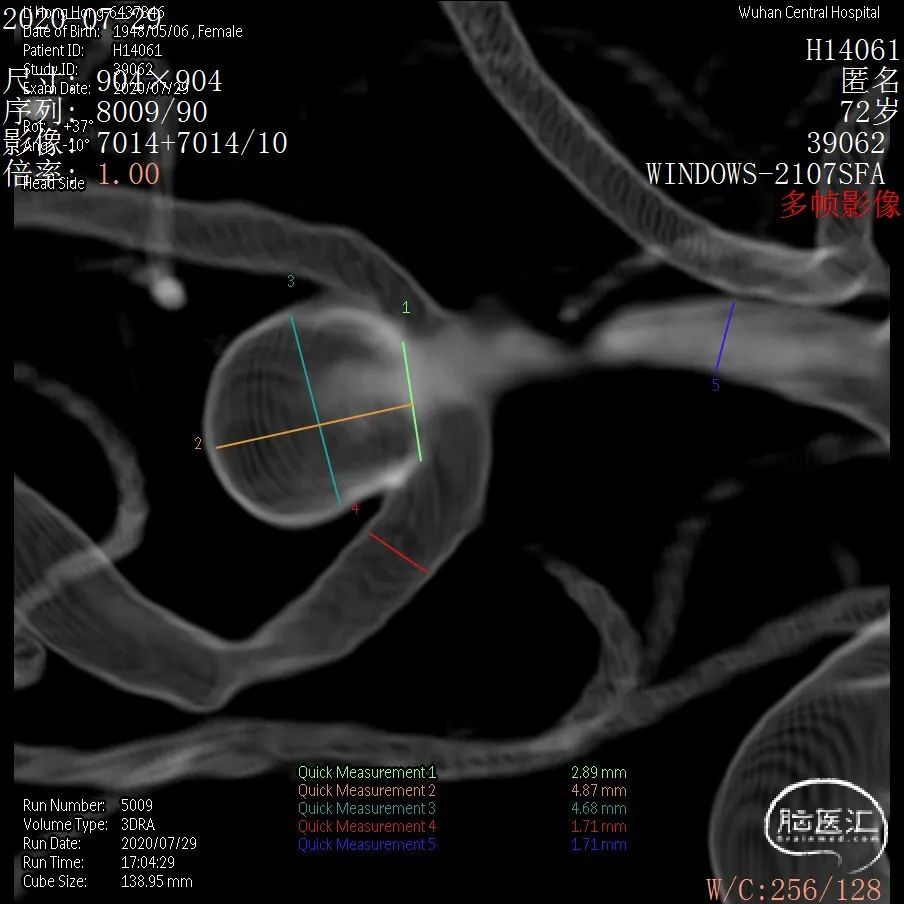

DSA结果:右侧大脑中动脉分叉部动脉瘤,约5.3*5.2mm,颈宽约2.9mm,形态囊状。

3D 和测量